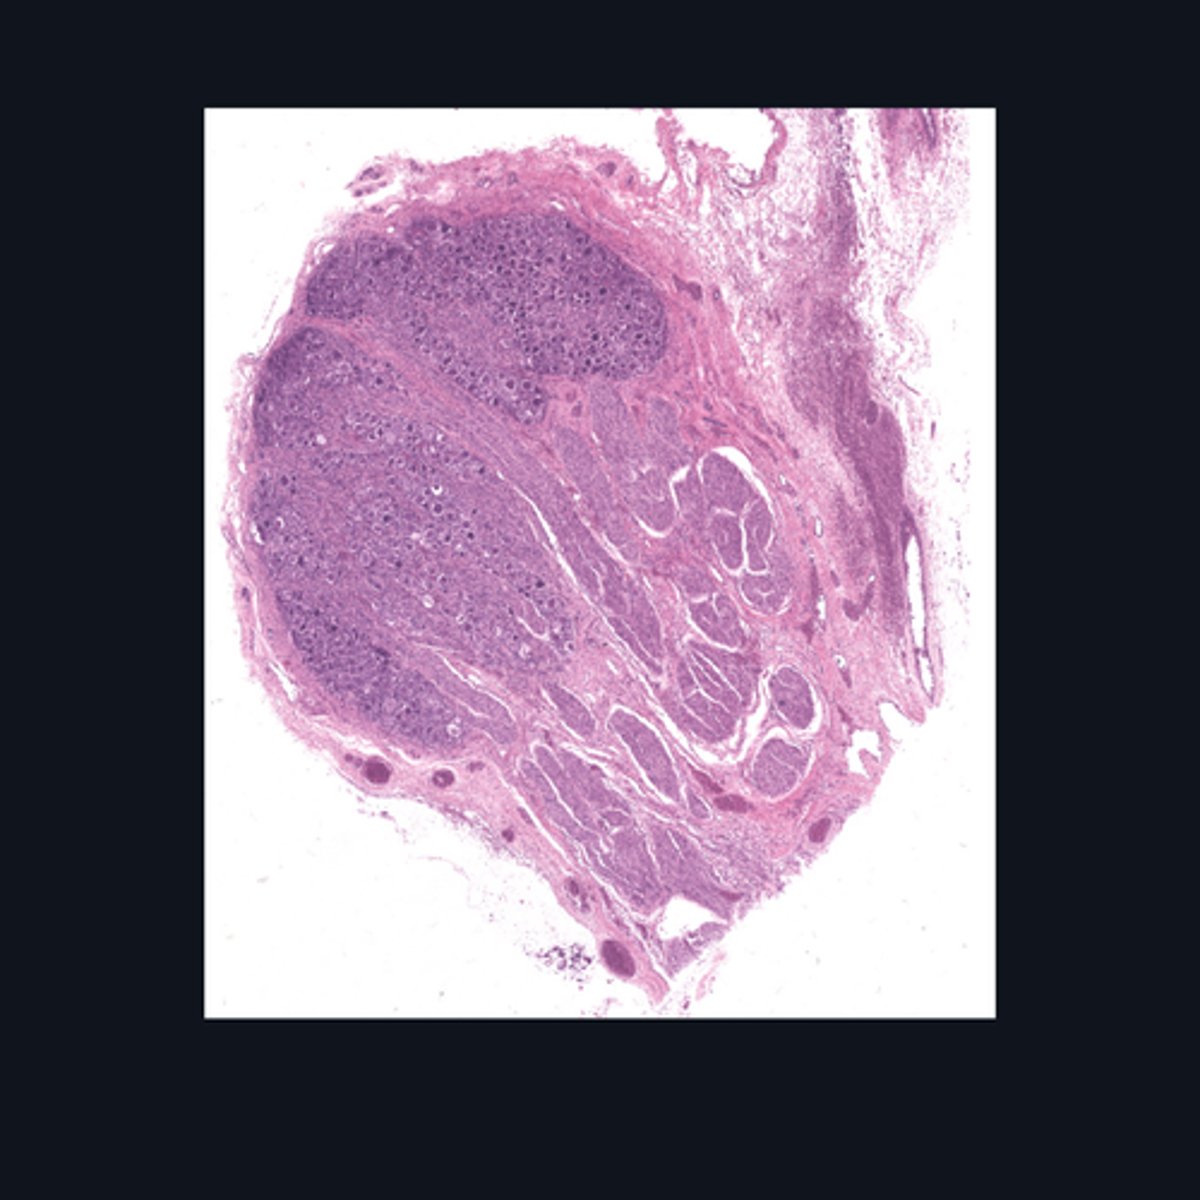

Brain, Cerebral cortex

Identify this structure.

Meninges

What covers this structure of the brain?

Sulci

Outer surface of cerebral hemisphere is highly folded to form convolutions known as

Plexiform (Molecular) Layer, Outer Granular Layer, Pyramidal Cell Layer, Inner Granular Layer, Ganglionic Layer, Multiform Cell Layer

What are the six poorly-designed layers of this structure?